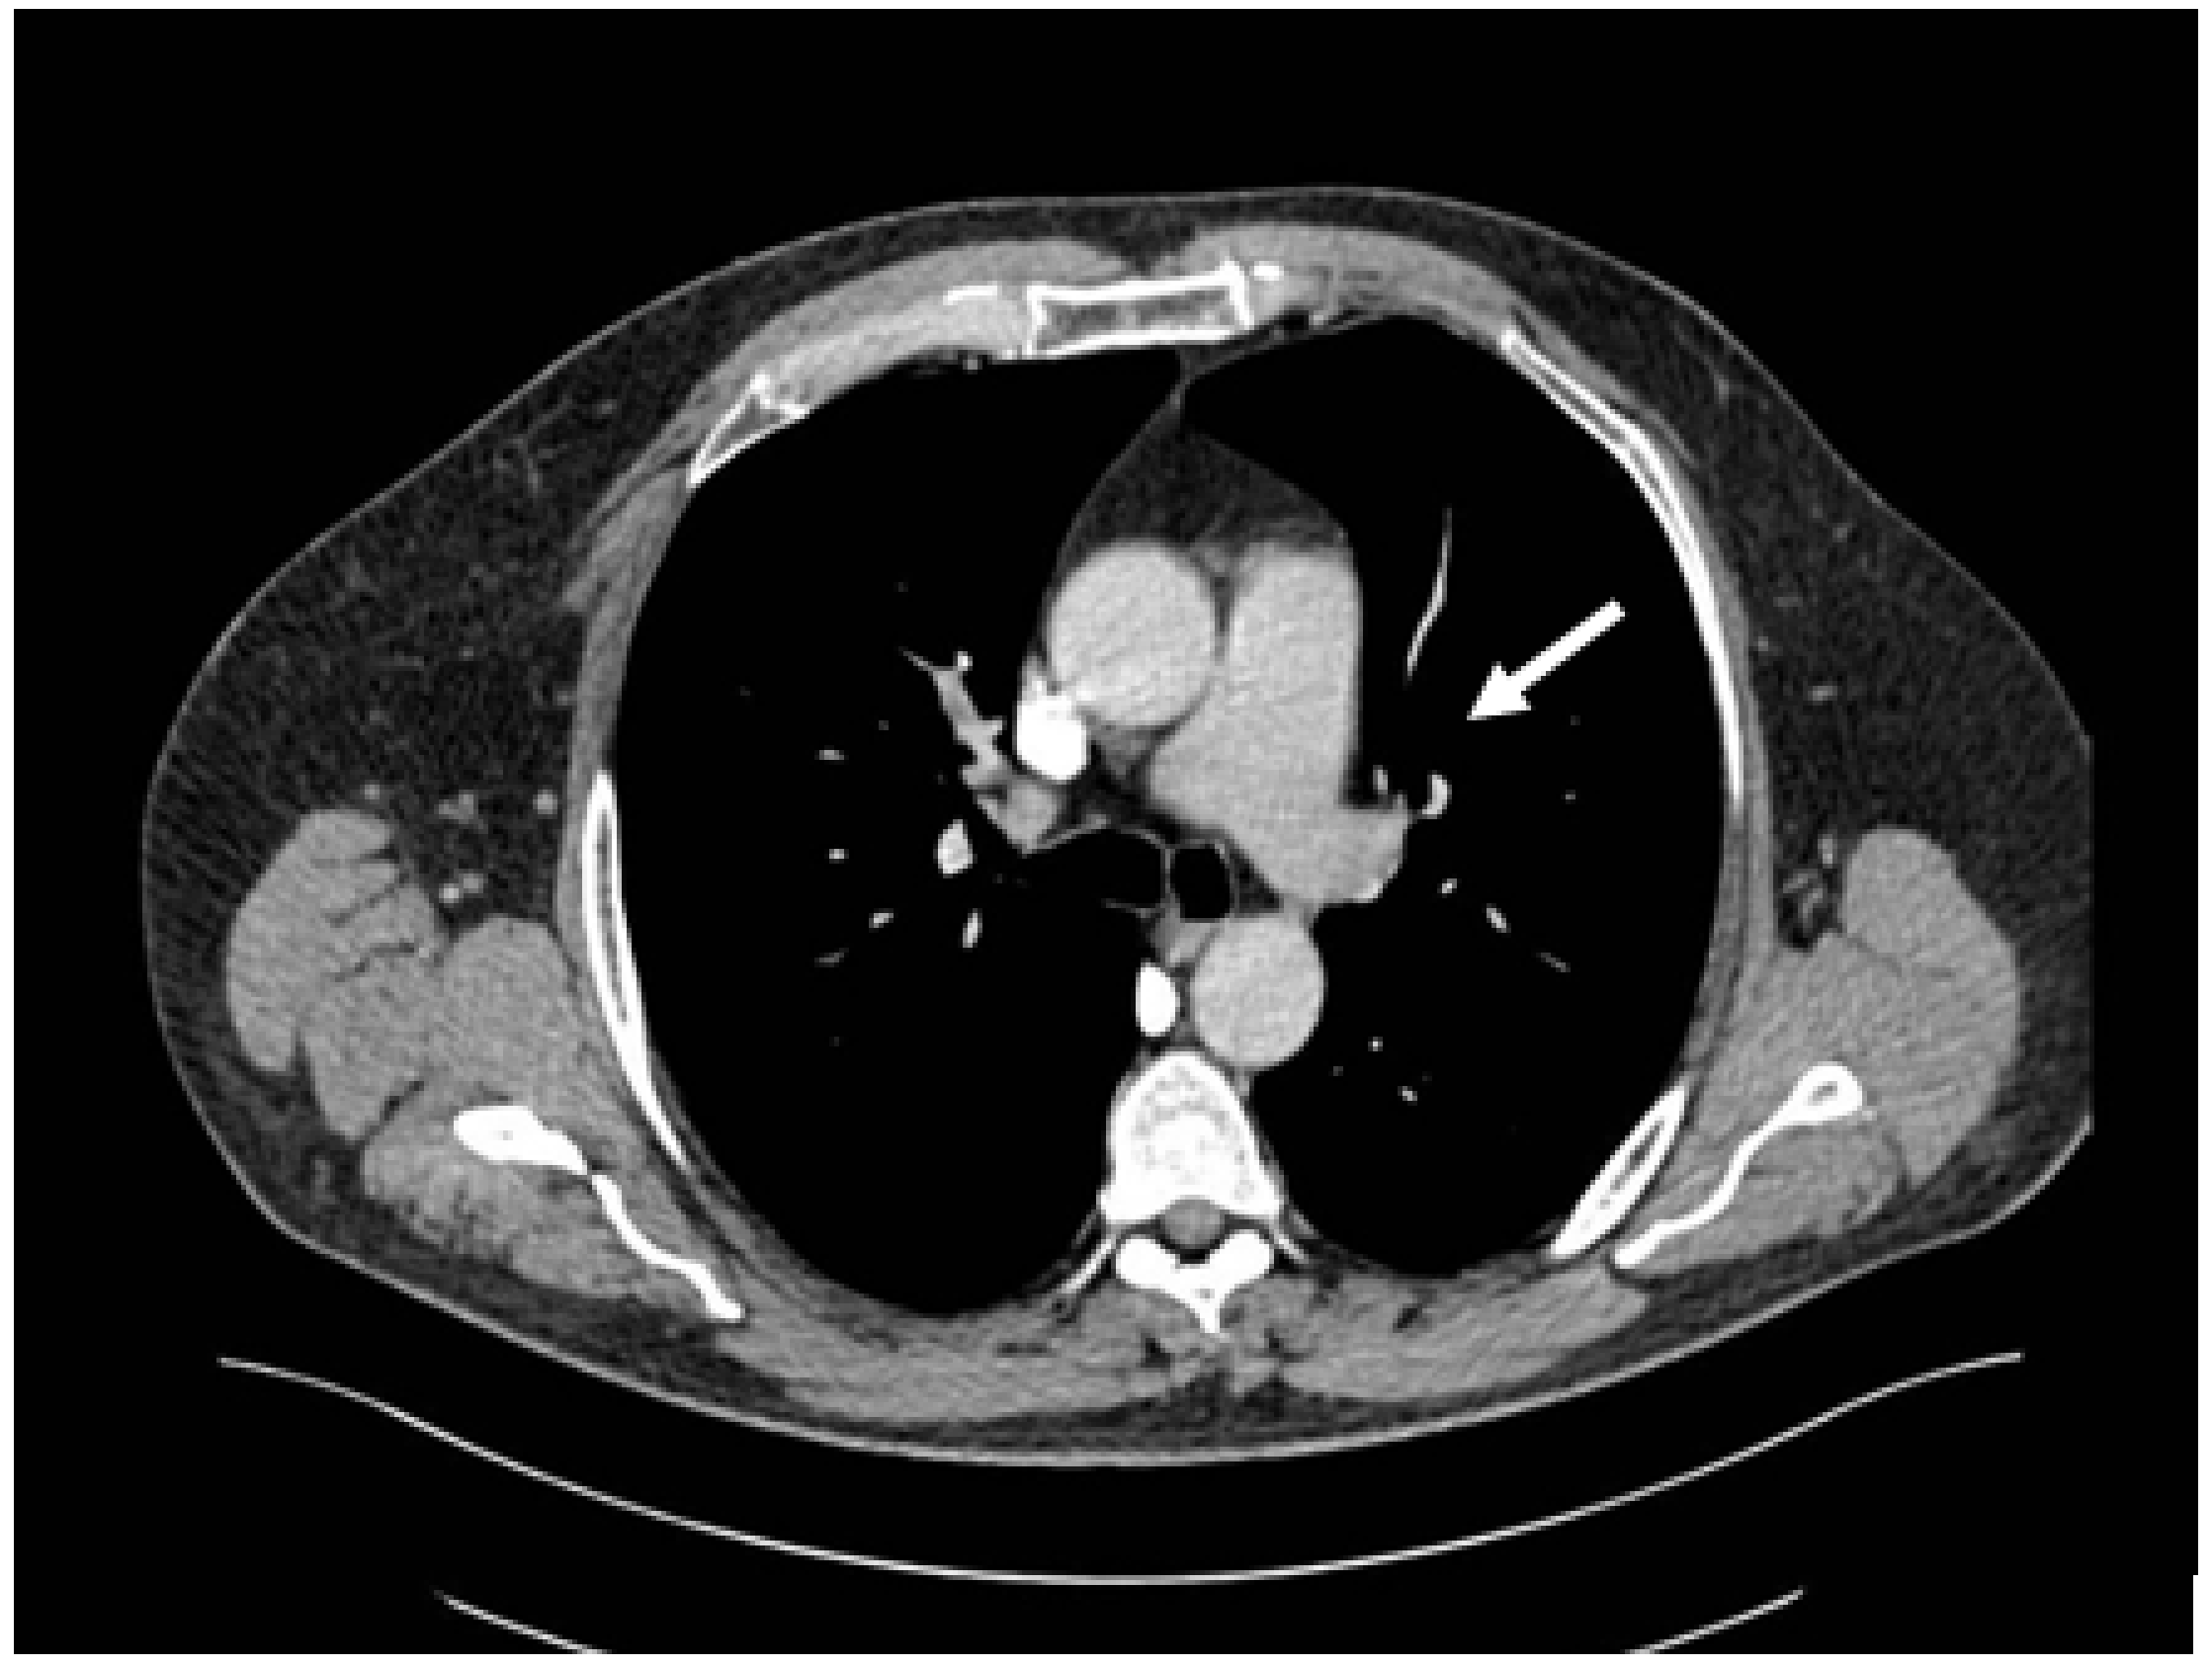

Figure 1. CT pulmonary angiography—pulmonary embolism, thrombus on the left main pulmonary artery (white arrow).

Out of the 13 patients, 3 patients had PE without evidence of DVT (0.60% of the total patients included in the study) (Figure 1).

Only one patient had concurrent traumatic injuries. This patient had a humerus fracture and underwent orthopedic surgery and immobilization. On day 34 after the burn injury, the patient was diagnosed with pulmonary embolism, with a thrombus on the right upper lobe pulmonary artery.